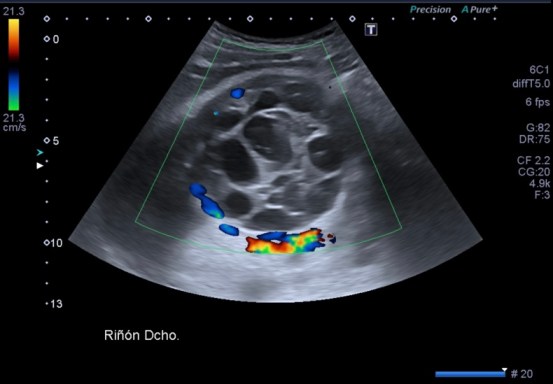

Lesión heterogénea, en el meso-riñón derecho, redonda, típica de quiste hidatídico.

Después de ver esta maravilla de imágenes, habiendo repasado el post 262 donde te explico las claves del quiste hidatídico, no tengo nada más que decir. Las imágenes hablan por si mismas. Perfectas, con una calidad increíble, el equipo increíble, bien ajustado, los parámetros adecuados, es un estudio perfecto, Sandra…yo lo sabía y te lo decía y estoy orgulloso, muy orgulloso de hacer esto que estoy haciendo ahora, en el día 2.

Un quiste hidatídico renal, maravilloso.